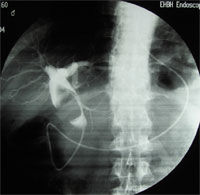

急性化膿性膽管炎造影圖片1.精神症狀。

1.膽管造影多採用PTC術,具有診斷和治療的雙重作用。可以發現擴張的膽管和梗阻的部位、原因,但嚴重休克病人一般不宜立即作此項檢查。